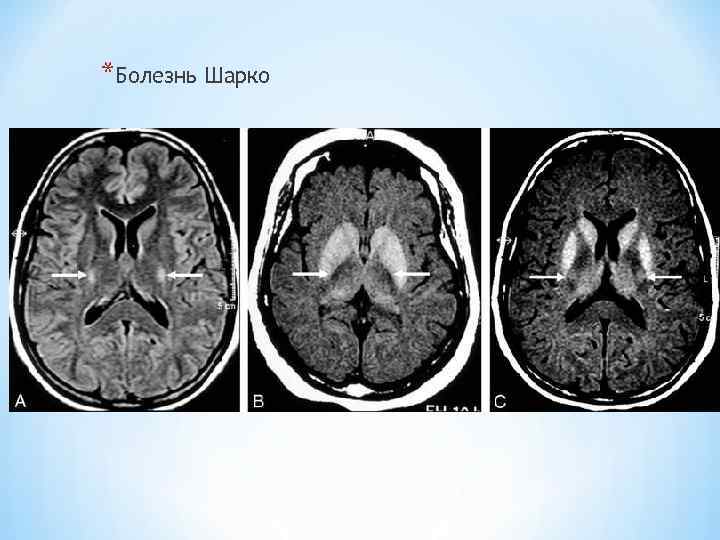

*Болезнь Шарко

*Болезнь Шарко